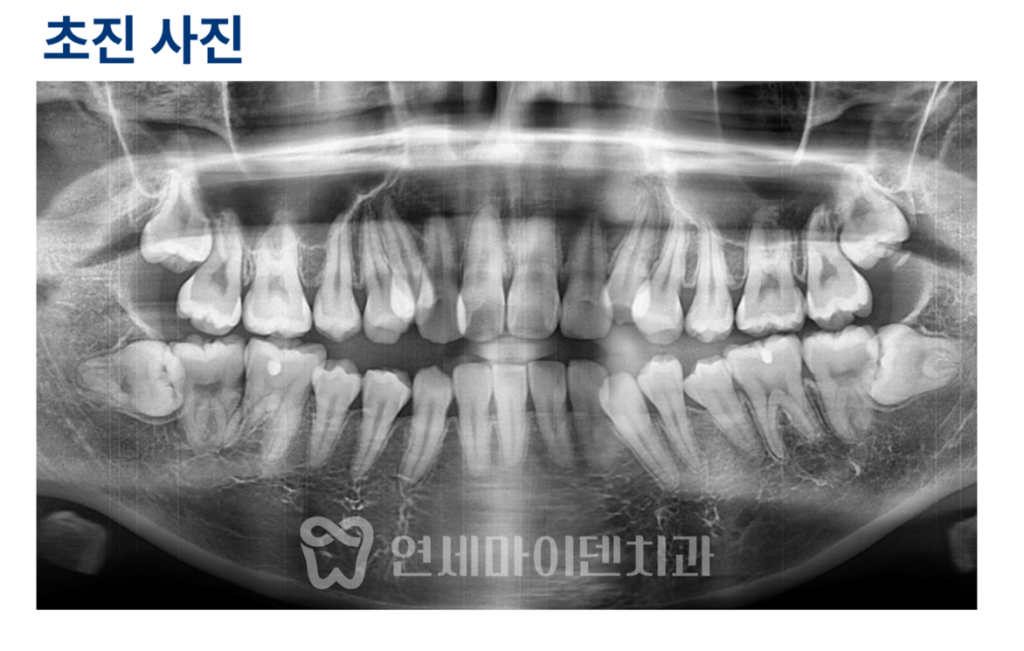

교정 전 치아 상태 분석

교정 전 환자분의 치아는

앞니부터 어금니까지 전반적으로 닿지 않는

개방교합 상태였습니다.

일부 어금니에만 교합력이 집중되면서

통증이 발생한 것으로 판단되었고,

치아 배열도 전체적으로 고르지 않은 상태였습니다.

방사선 사진을 살펴보면

사랑니가 4개 모두 존재했고,

송곳니와 작은 어금니가 겹치거나 기울어져 있어

치아 이동이 쉽지 않은 조건이었습니다.

또한 상악동의 위치가 낮고

치근 길이가 비교적 짧아

교정 과정에서 세심한 주의가 필요했습니다.